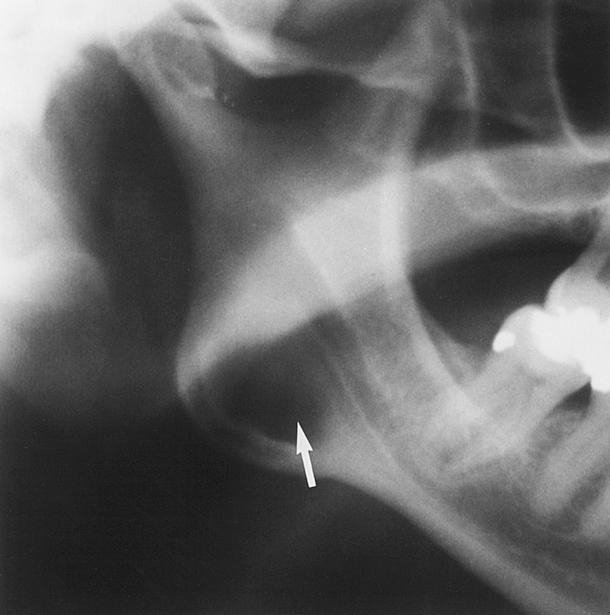

Uma paciente, 33 anos de idade, funcionária pública, compareceu a uma clínica radiográfica para realização de exames de imagem e documentação para colocação de implantes dentários. Sua história médica pregressa e sua saúde atual não apresentavam alterações dignas de nota. Após a realização dos exames radiográficos, constatou-se alteração óssea em mandíbula, assintomática, conforme mostra a radiografia a seguir.

Nessa situação, o diagnóstico clínico mais provável é o de